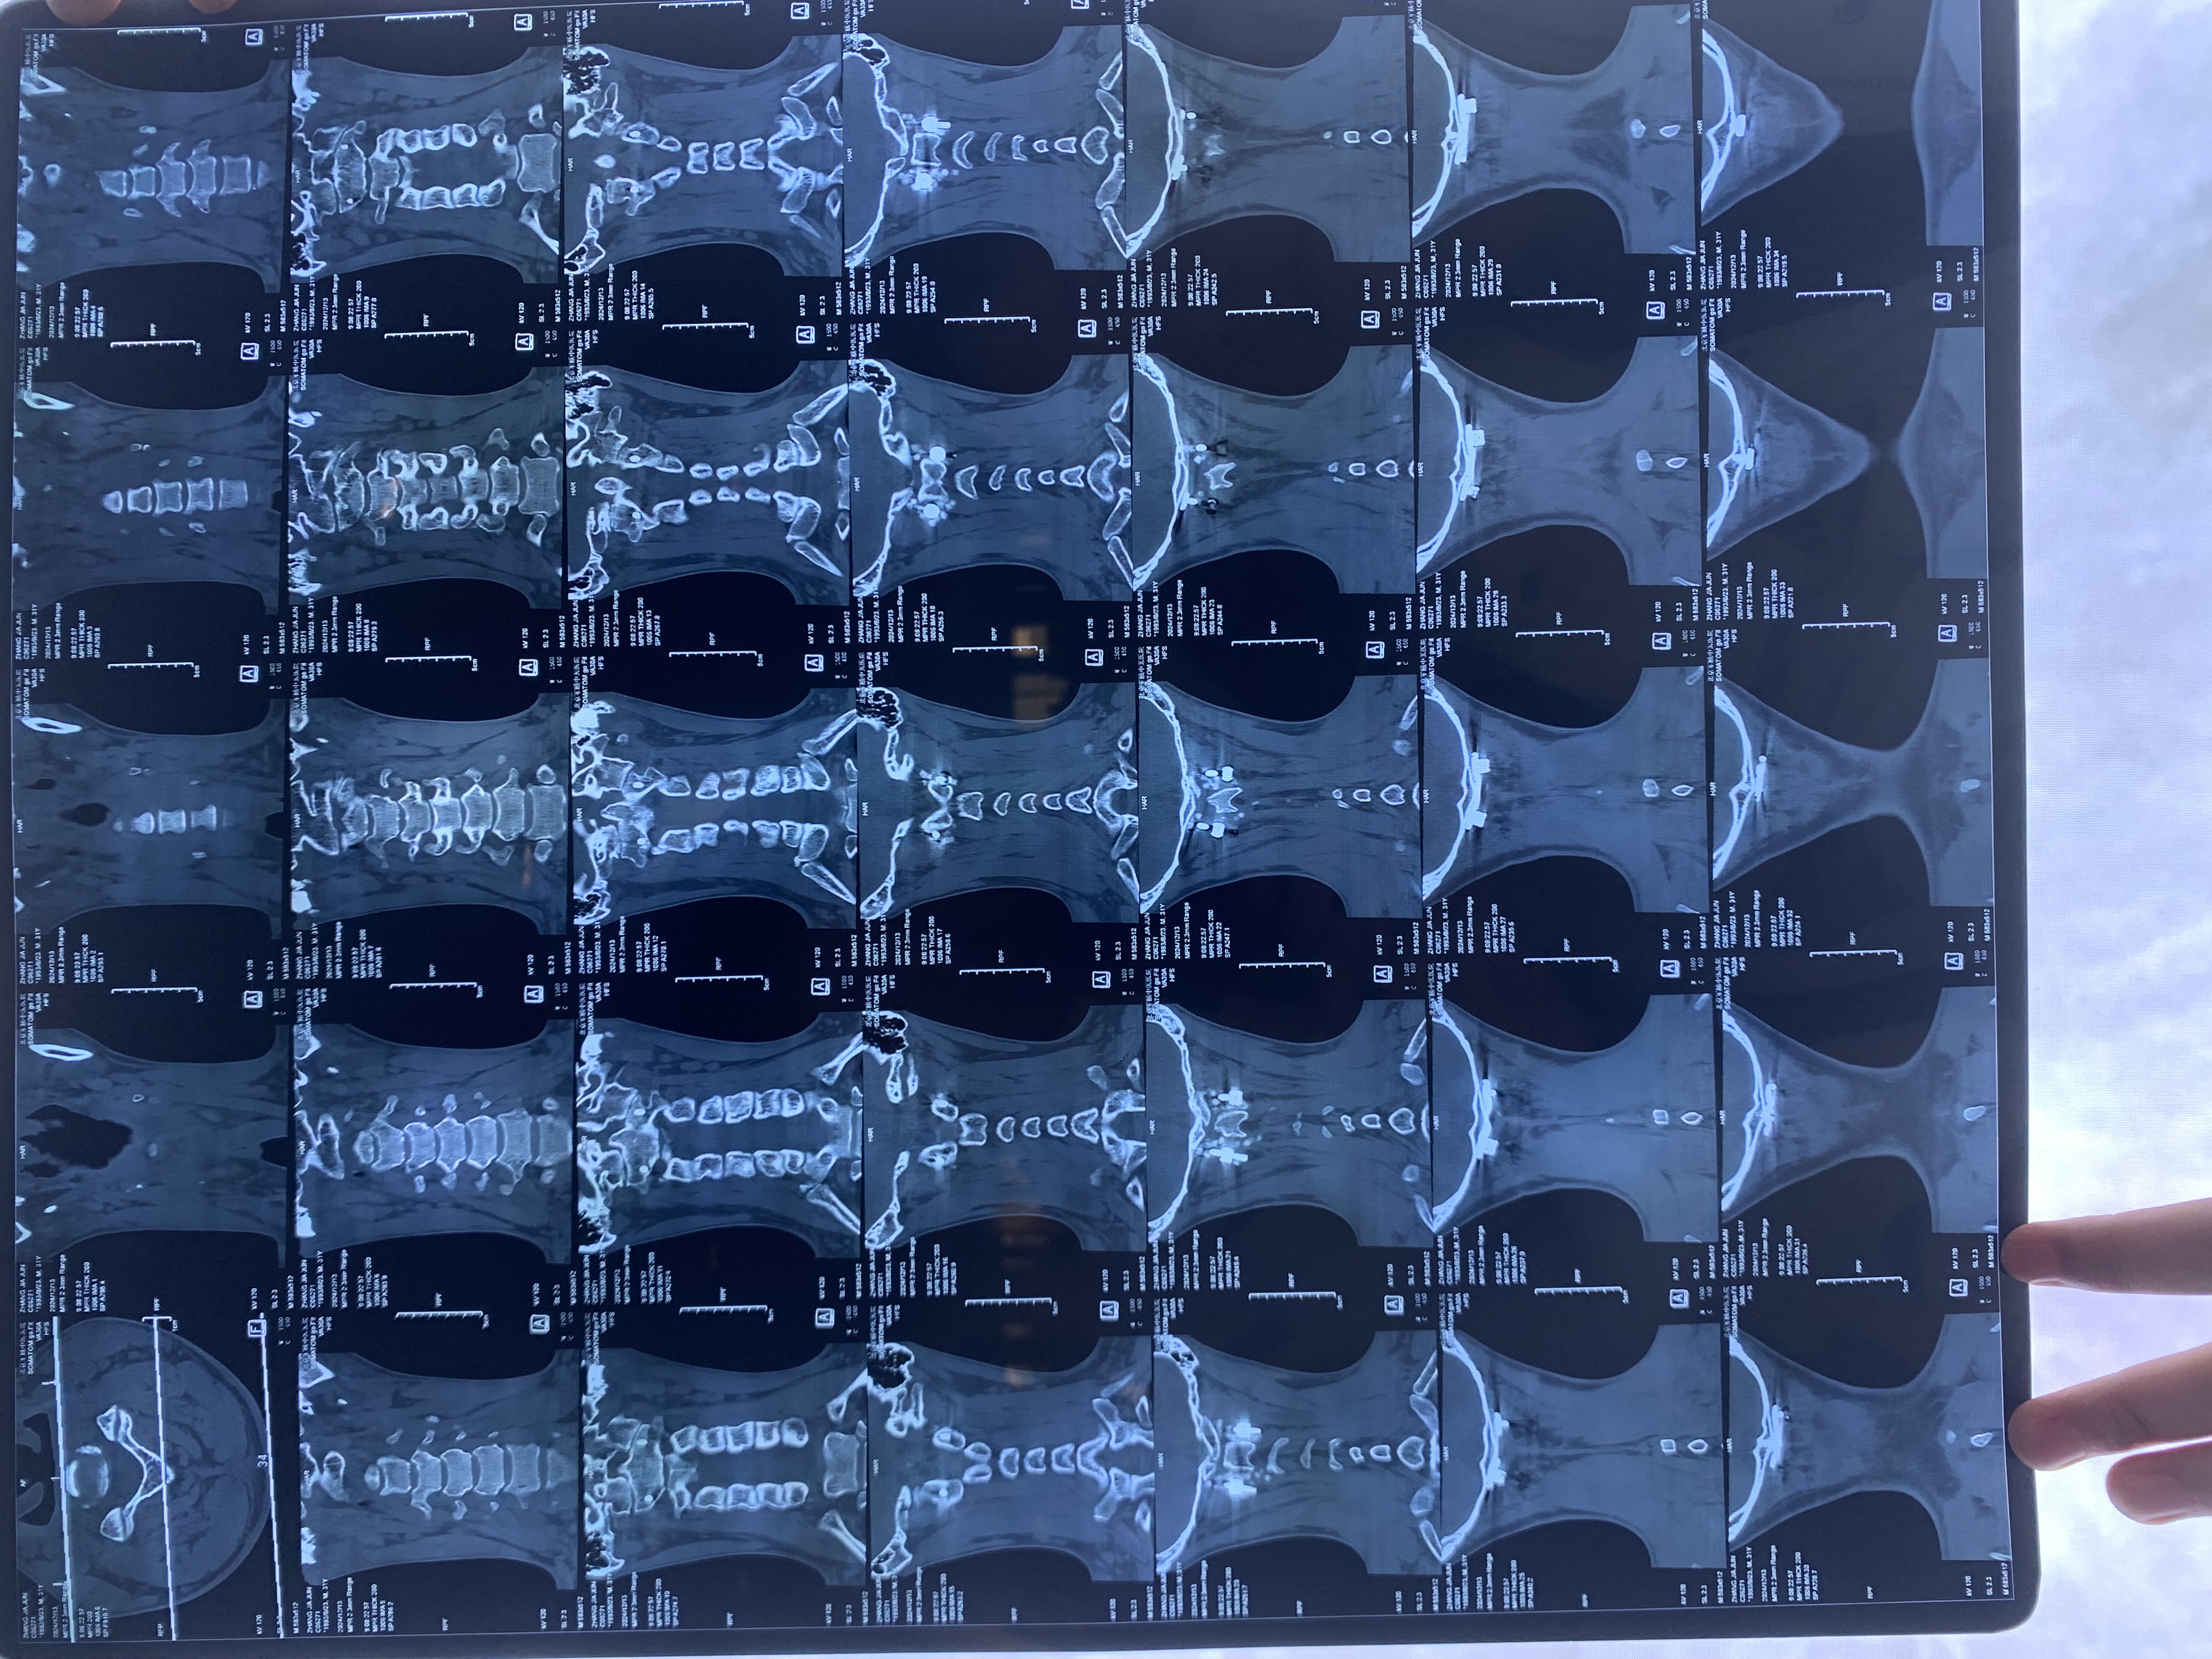

• 2024.12.13,去北京拍片,当天走路有点多,感觉脑袋里面疼。影像报告脱位和颅底凹陷都还在,影像如下: